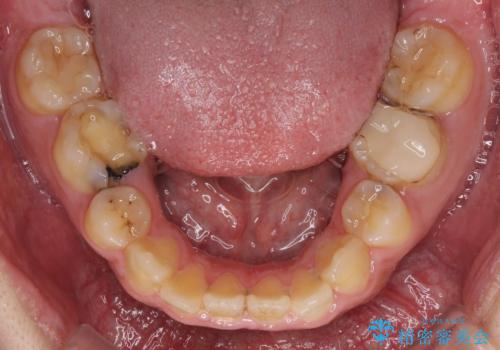

後戻りでデコボコの前歯 インビザライン矯正治療

- 高校時代に行った抜歯矯正が後戻りをしたとのことで来院された患者様です。

再矯正であることから、目立ちにくい装置を希望されたため、インビザラインにて矯正治療を行うこととしました。

下顎骨が左側に変位しているため、正中が合わないことは予想できましたが、歯列が整った後も咬み合わせが安定せず、咬み合わせを落ち着かせるために1年以上の期間を要しました。